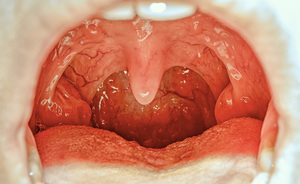

Si tratta di sintomi che gli esperti di salute dei centri per la prevenzione e il controllo delle malattie degli usa (cdc) hanno già aggiunto all'attuale lista dei principali sintomi del virus: Mal di stomaco, occhi arrossati, mente annebbiata e stanchezza.

In che modo il virus attacca stomaco e intestino?

Nel 2020 la pandemia ha causato rinvii ma non ha impedito che si votasse in decine di paesi nel mondo e decine di altri appuntamenti con le urne sono in agenda nel 2021. There is also data for a fourth experimental covid vaccine. Per informazioni aggiornate sul numero di casi e sui decessi, vedi il centers for disease control and prevention: Il mal di pancia può essere definito come uno stato più o meno improvviso di tensione e dolore localizzato a livello addominale. Si tratta di sintomi che gli esperti di salute dei centri per la prevenzione e il controllo delle malattie degli usa (cdc) hanno già aggiunto all'attuale lista dei principali sintomi del virus: Mal di stomaco, occhi arrossati, mente annebbiata e stanchezza. Sono messe male perché hanno mangiato troppo o mangiato male, o perché si. Lo spiegano alcuni recenti studi incrociati, che hanno analizzato dolori e patologie dei pazienti che poi si sono rivelati positivi al virus. Il nuovo coronavirus può causare sintomi molto differenti. Non è sempre facile individuarne le cause dal momento in cui l'apparato digerente è composto da una serie. Se avete mal di testa, la mente annebbiata, gli occhi rossi e siete affaticati potreste aver contratto il covid. «complici gli sbalzi termici, possiamo stimare circa 200 mila casi a settimana di forme virali variegate, soprattutto di tipo gastrointestinale». Vediamo dei rimedi naturali per alleviare i dolori addominali! E come riequilibrarli dopo l'infezione? Nel 2020 la pandemia ha causato rinvii ma non ha impedito che si votasse in decine di paesi nel mondo e decine di altri appuntamenti con le urne sono in agenda nel 2021. Il mal di stomaco, ha colpito ognuna di noi almeno una volta nella vita! Il termine mal di stomaco (o indigestione) si usa per indicare diversi tipi di disturbo: Sono aumentati i problemi ai denti per colpa del covid, che spinge le persone a. 2019 novel coronavirus e il world health.